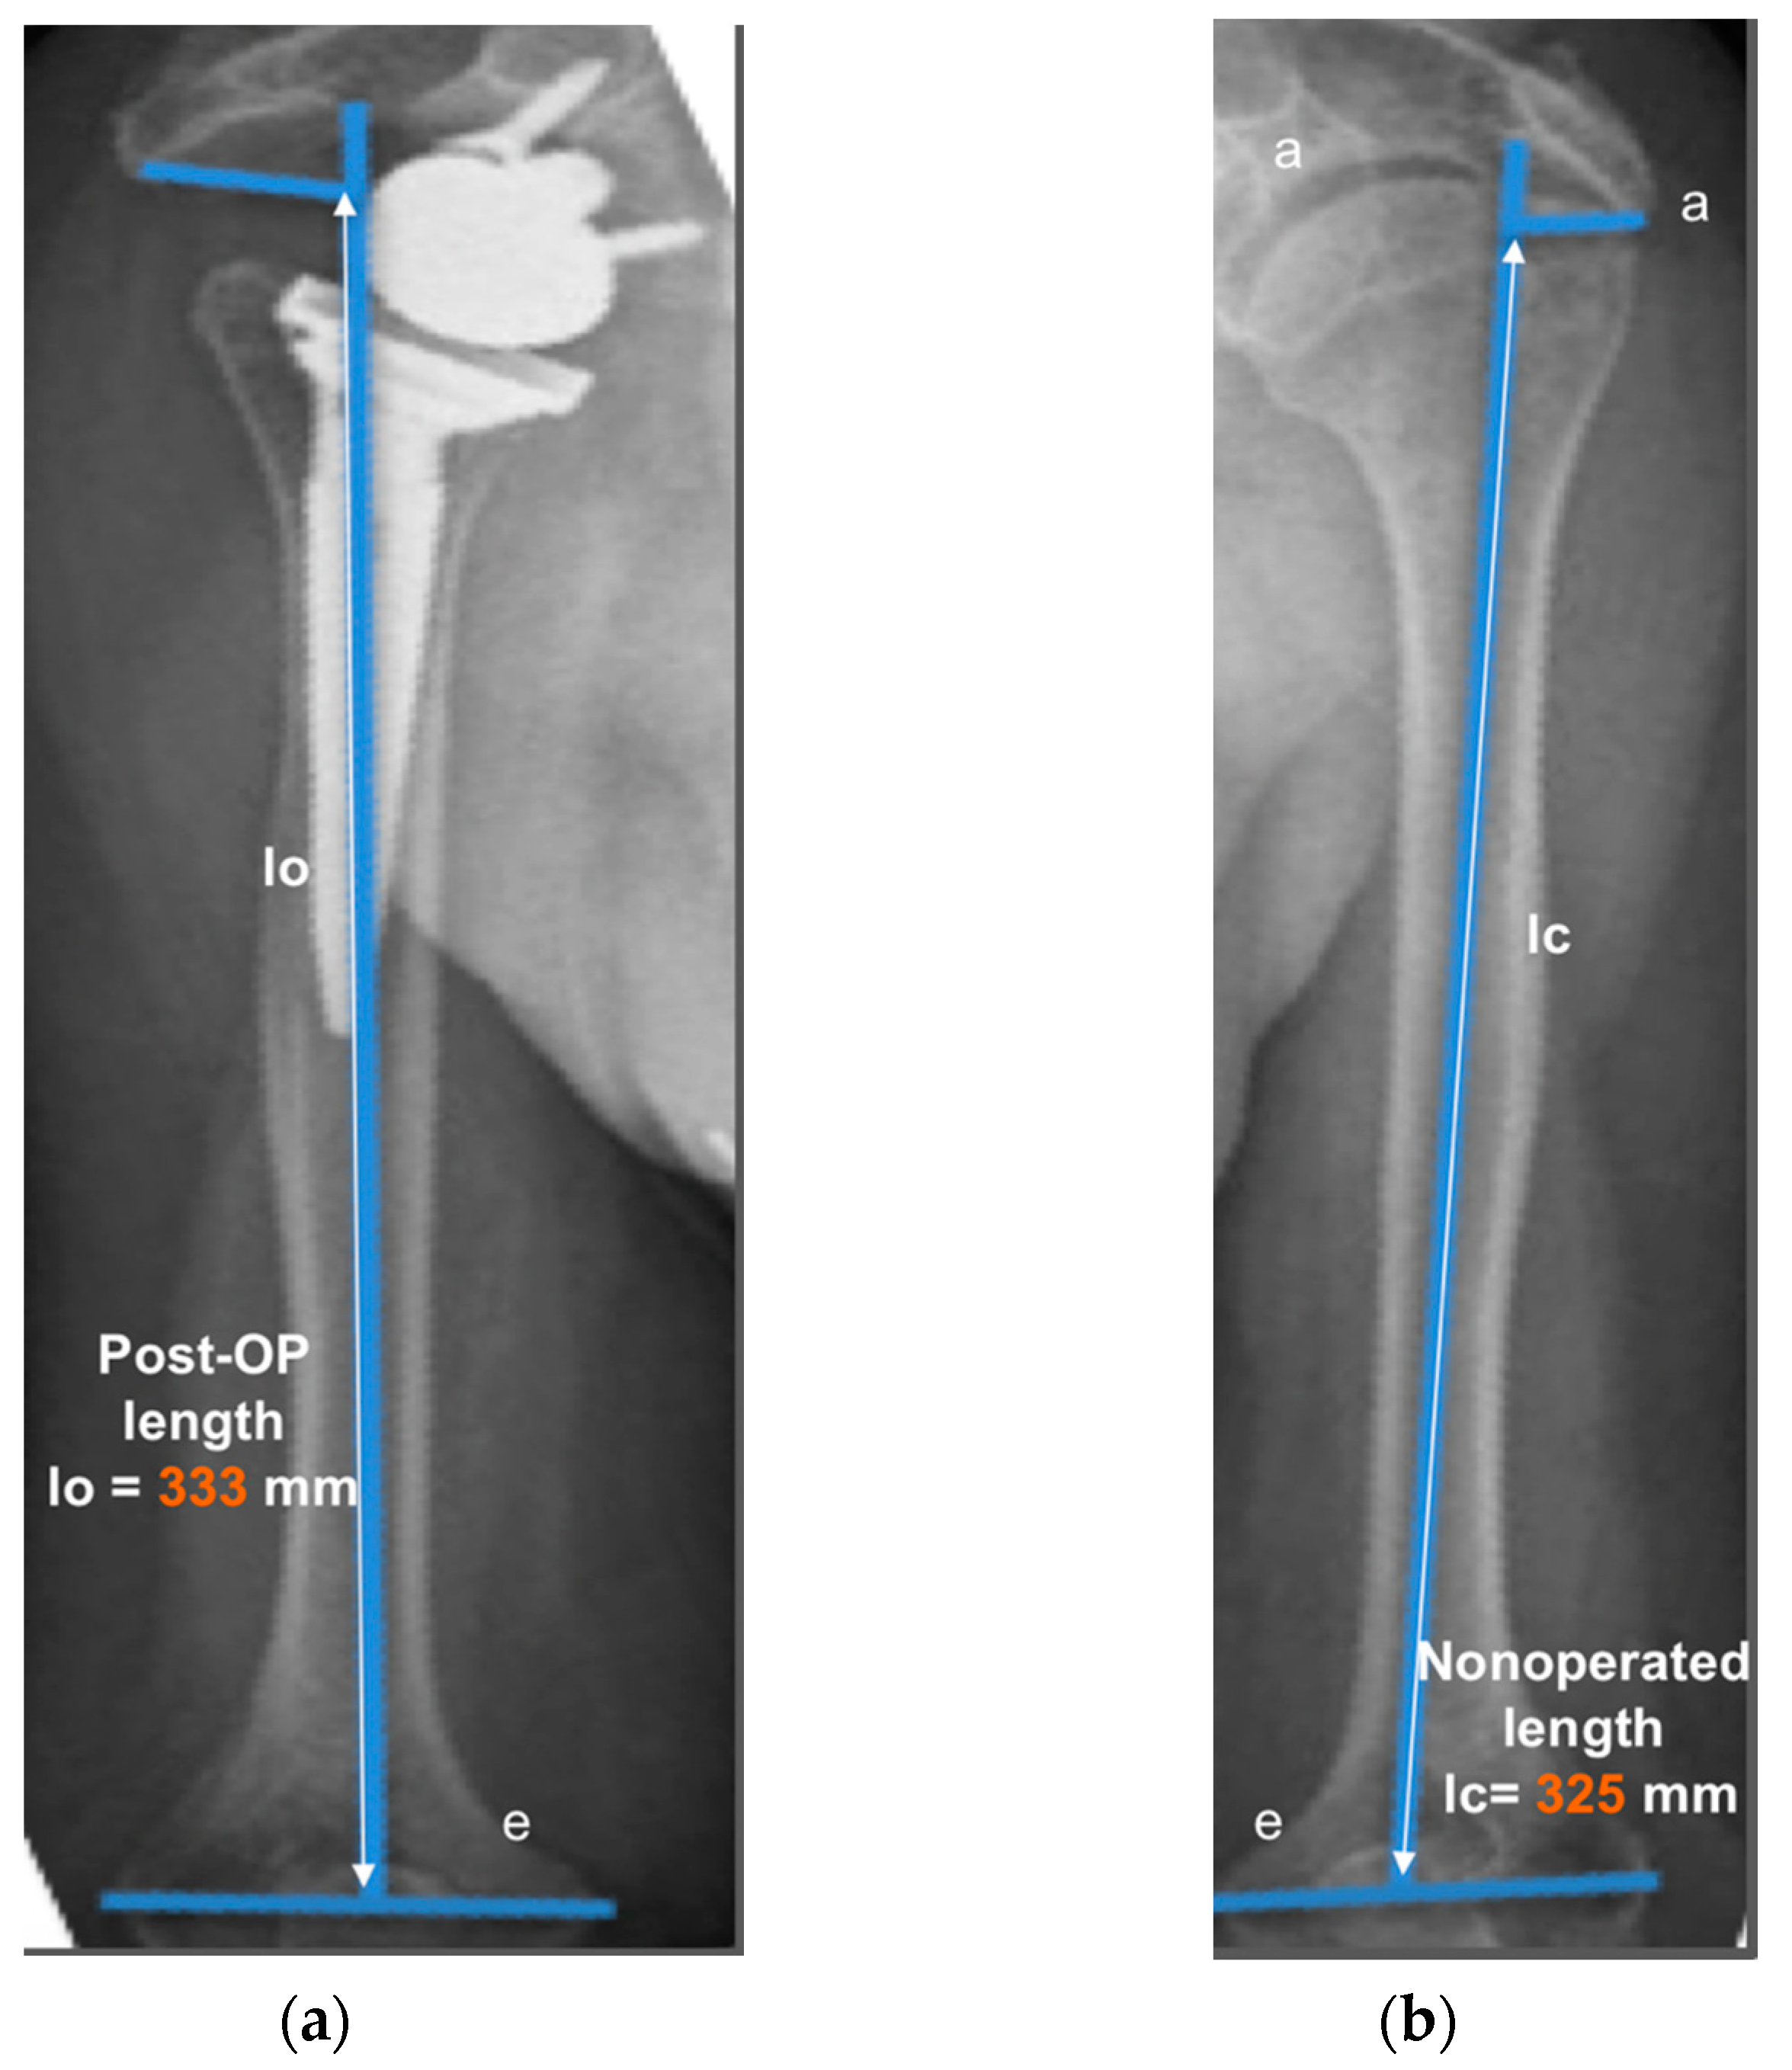

The operated side was evaluated both pre- and post-operatively on true antero-posterior shoulder radiographs obtained in neutral rotation, according to the protocol described by Greiner et al. [5]. The COR was located in the center of the base plate and the distance “m” to a vertical line on the outer border of the acromion was measured (Figure 1). Humerus length was evaluated post-operatively for the operated and non-operated side (Figure 2) according to the protocol described by Lädermann et al. [11]. True antero-posterior radiographs were taken in neutral rotation of the arm with the patients standing. The distance between the midpoint of the epicondylar line and a perpendicular line passing through the shaft axis from the most lateral point of the acromion was measured. All measurements were blinded and performed twice by two trained orthopedic surgeons not included the operating surgeon. Consensus decision by mean was found a posteriori. The reliability of radiographic outcomes was moderate to good with intraclass correlation coefficients (intra-session and inter-observer) comprised between 0.74 and 0.86 [12].

Figure 2.

Measurement of humerus lengthening according to the protocol of Greiner et al. [5] and Lädermann et al. [10]. The humeral shaft axis was drawn, and the distance between the two lines “a” (subacromial line) and “e” (inter-epicondylar line) was measured as the humerus length for the operated (lo) (a) and non-operated side (lc) (b). The difference between the operated and non-operated humerus length (∆l = lo − lc) was considered as humerus lengthening if lo > lc. (8 mm for this representative patient).

The distance “m” from COR consistently increased post-operatively (from 20.9 ± 3.3 mm to 36.2 ± 4.0 mm; p < 0.001) with a mean COR medialization of 15.3 ± 3.7 mm. Humerus length was longer on the operated (327 ± 21 mm) than on the non-operated side (321 ± 18 mm) with a mean humerus lengthening of 5.6 ± 7.7 mm (p = 0.011). No significant correlation was found between COR medialization and humerus lengthening (p > 0.05). Very large correlation coefficients were observed between shoulder adductor strength asymmetry and both COR medialization (r = −0.732; p < 0.001; Figure 10A) and humerus lengthening (r = 0.705; p < 0.001; Figure 10B). For all the other muscle groups, no significant correlations were observed between radiographic findings and strength asymmetries.